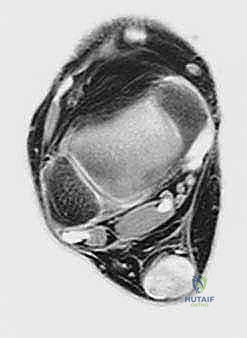

لفهم عبقرية هذه الجراحة، يجب أن نفهم التشريح. وتر العضلة المثنية الطويلة لإبهام القدم (Flexor Hallucis Longus - FHL) هو وتر يمر في الجزء الخلفي من الساق، قريباً جداً من وتر أخيل، ويمتد نزولاً ليتحكم في حركة انثناء إصبع القدم الكبير.

3. القرب التشريحي: يقع وتر FHL مباشرة بجوار وتر أخيل، مما يسهل عملية النقل الجراحي دون الحاجة لشقوق جراحية واسعة في أماكن بعيدة.

4. التروية الدموية: يتمتع وتر FHL بتروية دموية ممتازة، وعند نقله إلى وتر أخيل التالف، فإنه يجلب معه إمداداً دموياً جديداً يساعد في التئام الأنسجة المتضررة.